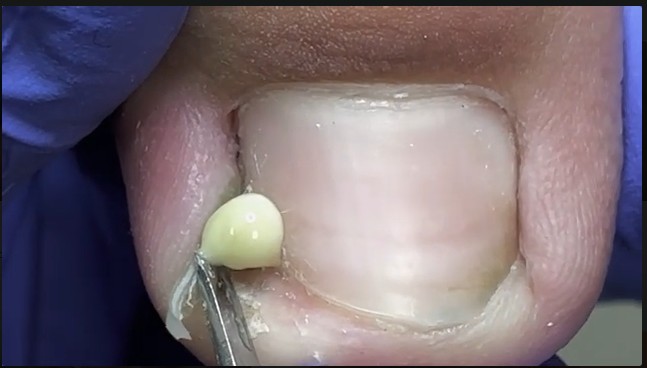

The image above shows a clear case of a nail fold infection, where thick yellow pus has formed along the edge of the nail. This condition, commonly known as paronychia, occurs when bacteria enter the skin around the nail and begin to multiply. Although it may appear small, this type of infection can be surprisingly painful and may worsen quickly if not treated correctly.

The presence of pus indicates that the infection has reached an advanced stage. At this point, topical treatments alone are often not enough. The trapped fluid creates pressure that can slow healing and increase pain. If left untreated, the infection may spread deeper into the finger or affect the nail matrix, potentially causing nail deformities.

Professional drainage allows the pressure to be released safely, reducing pain and helping the body heal more efficiently.

A nail fold infection with pus is more than a cosmetic concern—it is a medical issue that requires proper care. The image above highlights how quickly a small injury can turn into a painful condition. With early treatment and good hygiene, nail infections can heal safely, restoring comfort and nail health.